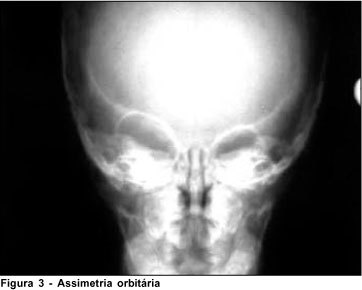

Realizou-se radiografia da face e ultra-sonografia ocular bilateral, mostrando olho direito com comprimento axial de aproximadamente 22 mm e cavidade vítrea normal (Figura 3).